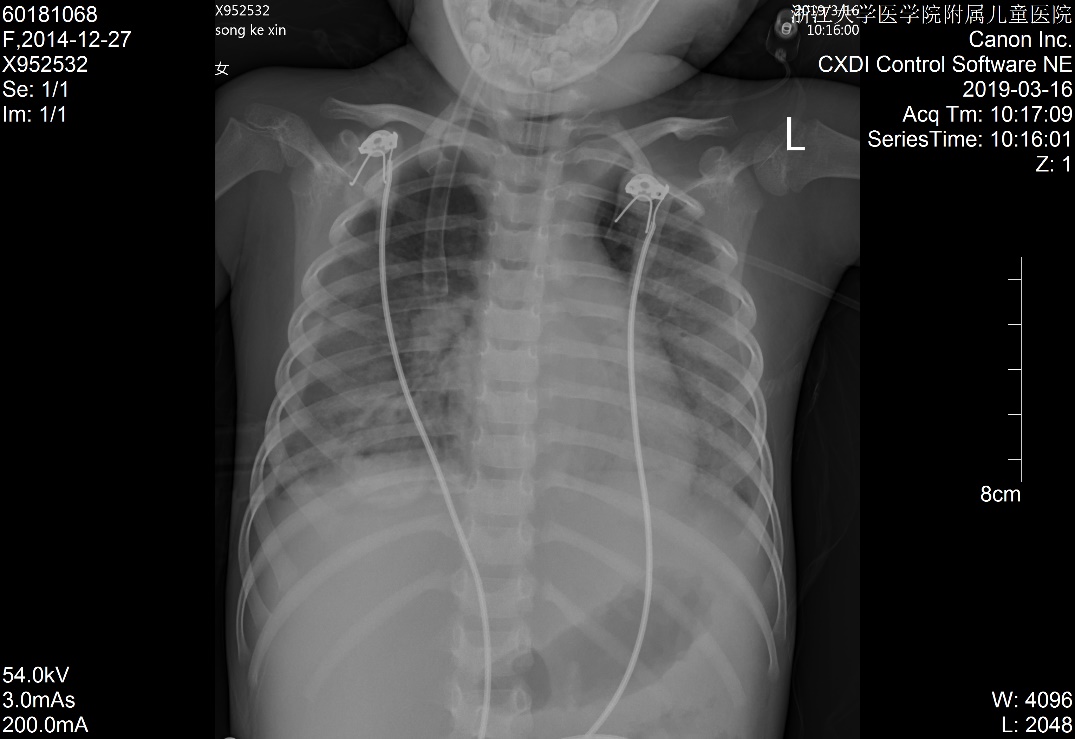

1 资料与方法患儿女,5岁2月,因“多尿、多饮、多食3个月余,意识不清1天余”由外院转入。3个月余前出现多尿、多饮、多食,家长未重视,未就诊。1 d前出现意识不清,并抽搐3次,急送当地医院就诊,当时查体情况具体不详,查血气电解质示pH 6.87,pCO225.9 mmHg,Na+ 125.4 mmol/L, Glu 17.1 mmol/L,Lac 1.1 mmol/L,HCO3- 4.6 mmol/L,ABE -28.1 mmol/L。考虑诊断“糖尿病、糖尿病酮症酸中毒、脑水肿?”收住当地医院。在当地医院住院期间,予大量补液[约3 L/24 h,大部分为晶体液,可能因为低血压,因住院期间曾使用多巴胺10 μg/(kg·min)维持],住院期间出现氧饱和度不能维持,遂予气管插管并机械辅助通气。因病情持续恶化,联系后转入本院PICU。既往史、个人史、出生史无殊。爷爷及外婆有糖尿病及高血压病。入院查体:T 37.8℃,脉搏:146次/min,呼吸:38次/min(为机械通气),血压98/77 mmHg(1 mmHg=0.133 kPa),无特殊面容及畸形,体质量:11 kg,气管插管带入,经皮血氧饱和度95%,镇静状态,双侧瞳孔等大等圆,直径2 mm,对光反射存在,颈软,余神经系统无明显阳性体征,面色苍白,消瘦貌,双肺呼吸音粗,可闻及湿啰音,腹软,肝脾肋下未及,皮肤弹性略差,肢端凉,毛细血管充盈时间5 s。入院后查白细胞计数8.52×109/ L-1,淋巴细胞15.4%,中性粒细胞82.0%,超敏C反应蛋白17.33 mg/L;血气分析:pH 6.996,pO2 91 mmHg, pCO2 43.5 mmHg,Na+ 126 mmol/L,Glu 21.0 mmol/L,Lac 2.9 mmol/ L,HCO3- 10.1 mmol/L,ABE -20.6 mmol/L;血氨63 μmol/ L;生化五类:总蛋白34.9 g/L,白蛋白26.5 g/L,丙氨酸氨基转移酶24 U/L,天门冬氨酸氨基转移酶96 U/L,肌酐147 μmol/L,尿素12.38 mmol/L,肌酸激酶1 680 U/L,肌酸激酶-MB活性166 U/L,甘油三酯6.05 mmol/L,胆固醇6.11 mmol/L,淀粉酶3 094.5 U/L;尿常规:尿酮体++,尿蛋白++,尿糖++++,尿隐血+++;糖化血红蛋白16.5%;血清C肽测定:0.116 nmol/L;糖尿病自身抗体阳性;脑脊液常规、生化及培养无殊;血尿培养阴性;胸片:两肺弥漫性病变,双侧胸腔积液,肺水肿待排(图 1);心超:左室收缩功能稍减低(EF 0.53),少量心包积液,二、三尖瓣轻度反流;腹部B超:肝大、腹腔积液。考虑诊断“急性呼吸窘迫综合征、急性肾功能损伤、1型糖尿病、糖尿病酮症酸中毒、脑水肿、多浆膜腔积液”,予呼吸机支持[HFO模式,FiO2:85%,f:5.8 HZ,ΔP:36 cmH2O(1 cmH2O=0.1 kPa),MAP:25 cmH2O, OI:23)、多巴胺及肾上腺素泵注维持血压、甘露醇降颅压、胰岛素注射降血糖及其他对症支持治疗,患儿入院第3天酮症酸中毒基本纠正,第6天改无创通气(CPAP,Flow:10 L/min,PEEP:4 cmH2O),入院第10天改大气吸入,复查胸片基本好转(图 2),住院期间未再抽搐,在停呼吸机机械通气镇静后意识好转,但较激惹、躁动,肾功能逐步恢复,住院28 d后出院,出院前患儿意识清,能完成日常对答,查头颅MRI提示脑萎缩改变,复查肺部影像学未出现遗留性病变,复查心超未见心包积液。现规律随访近一年,胰岛素治疗血糖控制尚可,未遗留明显神经系统、呼吸系统等后遗症。本研究经浙江大学医学院附属儿童医院伦理委员会批准(批准号:2020-IRB-078),并经患儿家属知情同意。

| 图 2 入院第10天胸片 |

本例患儿,既往没有慢性肺部疾病及心脏疾病的情况下,急性起病,并呈进行性低氧血症,伴X片改变,且心超不支持左心功能不全,虽有液体超负荷的病史,但经积极的限液利尿治疗,其氧合指数(OI)仍≥ 16,故诊断ARDS[3-4]。另曾有报道DKA合并纵膈气肿的[5],但本病例胸片未提示气肿。